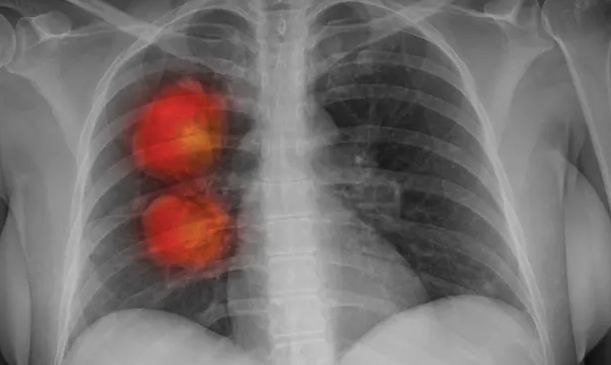

زیرەکی دەستکرد دەستنیشان دەکات کە ئایا کۆمەڵی ناسرووشتی کە لە سی تی سکان  دەستنیشانی دەکات کە ئایا بارستەیەکی نائاسایی کە لە سی تی سکاندا دۆزراوەتەوە شێرپەنجەیی یە یان نا. بەگوێرەی بڵاوکراوەکە، ئەو بە کارایییەکی بەرزەوە ئەم کارە دەکات، کە لە داهاتوودا ڕەنگە یارمەتیدەر بێت لە دەستنیشانکردنی شێرپەنجە لە قۆناغێکی سەرەتاییدا.

زیرەکی دەستکرد بە پێی داتاکانی سی تی سکان لە نزیکەی ٥٠٠ نەخۆشی تووشبوو بە وەرەمی سییەکان بەدی هات . لە کاتی تاقیکردنەوەدا مۆدێلەکە نزیکە لە ئایدیاڵ. ئێستا گەشەپێدەرەکان پلانیان هەیە زیاتر لەسەر نەخۆشەکان لە کلینیکەکاندا تاقی  بکەنەوە